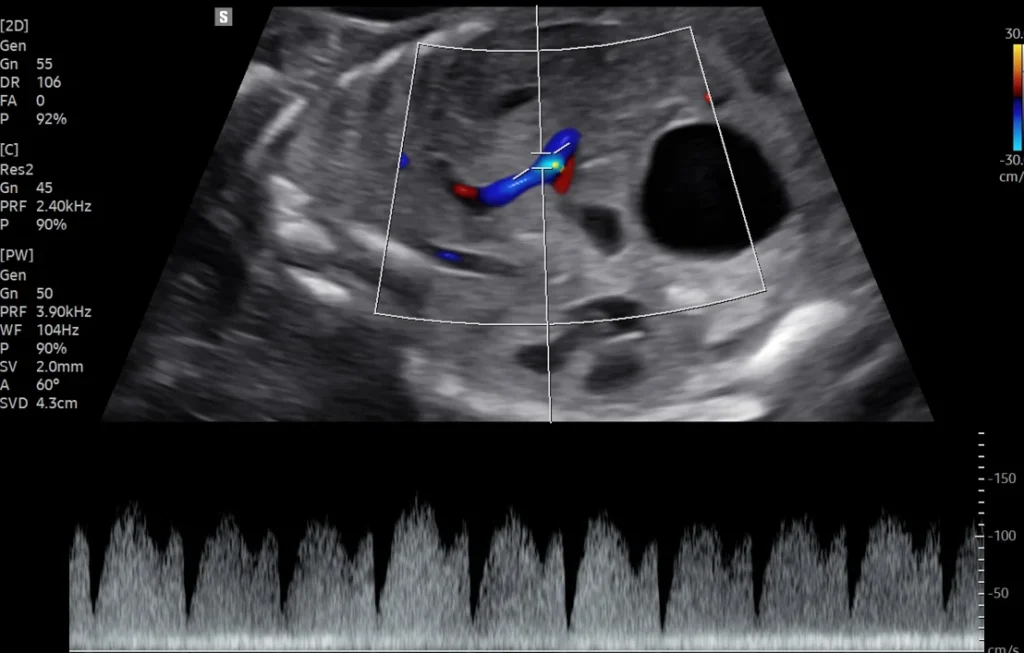

Fetal Doppler Studies (30-34 weeks)

Assessment of fetal circulation in:

• IUGR

• High-risk pregnancy

• Preeclampsia

• Twin–Twin Transfusion Syndrome

• Gestational diabetes & hypertension